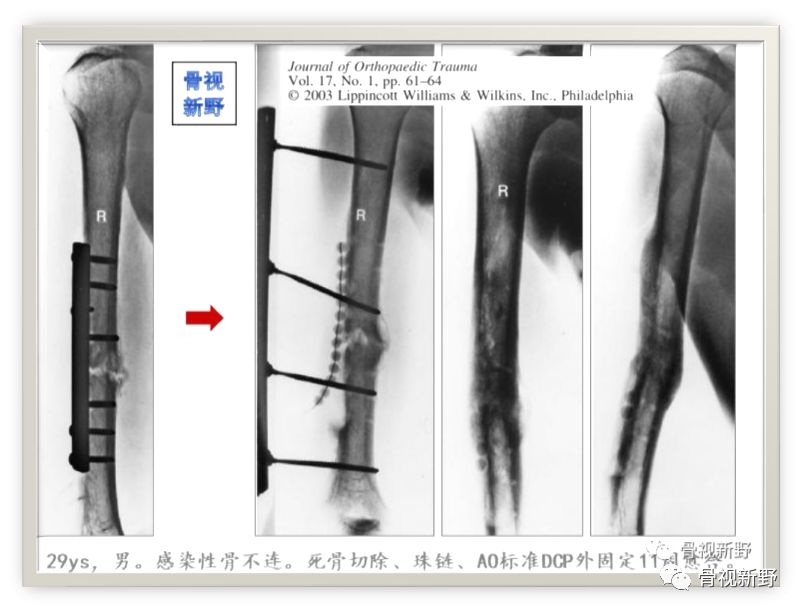

第三次报道

2003年,Rene K.Marti团队再次报道了将AO标准钢板作为外固定架用于开放性骨折以及骨感染性骨不连的固定病例31例,也取得了较好的疗效。

Cases